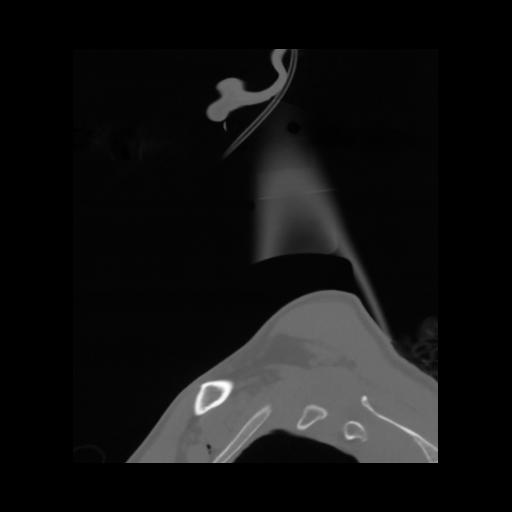

14 P.BLANDAS,,Sagittal,2.000,P.BLANDAS,Sagittal,